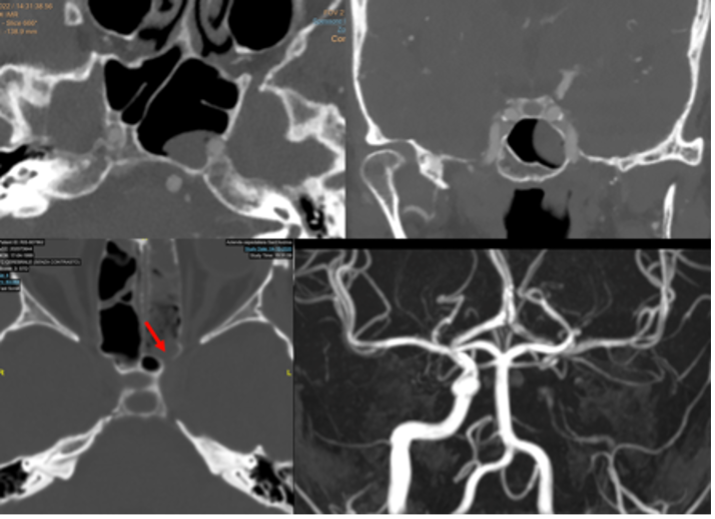

Anteriormente alla sella turcica si trova il seno sfenoidale, soggetto a una considerevole variabilità di dimensione, forma e pneumatizzazione. Il seno sfenoidale è attraversato da setti, assai variabili come numero, forma, direzione, spessore. La loro valutazione può essere oggetto di studio mediante tomografia computerizzata (TC) in caso di pianificazione per intervento per via trans-sfenoidale (fig 2).

Figura 2

Sezione TC sagittale e coronale

In questi casi è importante anche valutare l’integrità della parete del seno sfenoidale, che può essere molto sottile o assente e consentire all’arteria carotide interna di aggettare direttamente verso il seno protetta da sola mucosa. Questa condizione è ovviamente estremamente pericolosa per la possibilità di lacerare l’arteria durante un intervento per via trans-sfenoidale (fig 3) (3).

Figura 3

Variante anatomica con procidenza della carotide interna nel seno sfenoidale

In basso le immagini post-operatorie con l’occlusione dell’arteria carotide interna